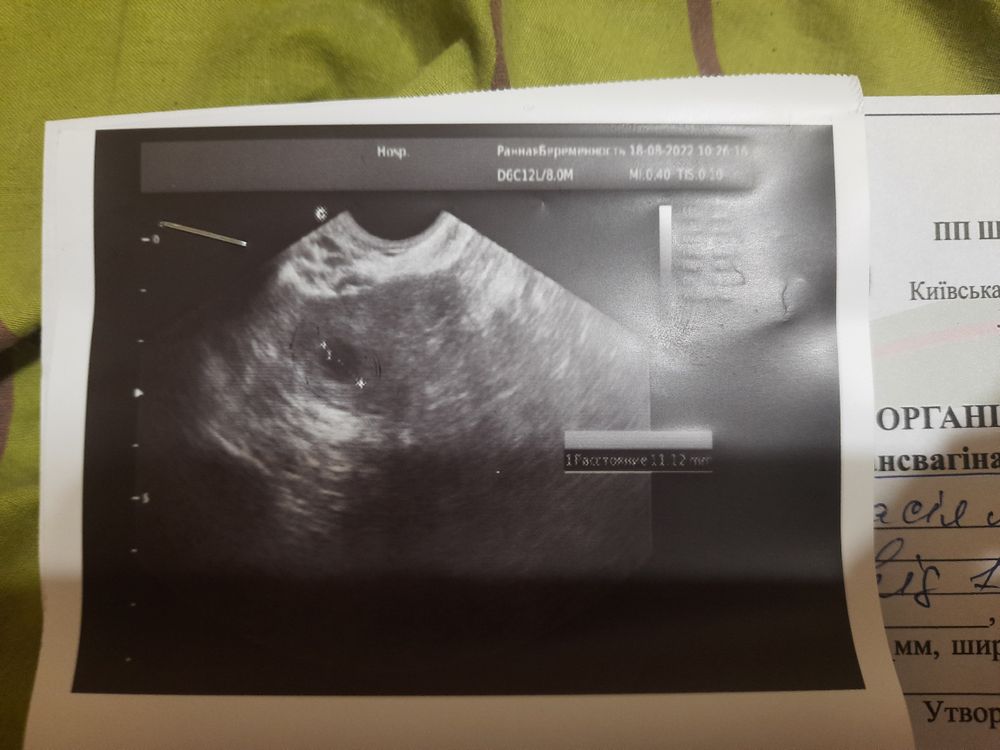

Записалась на узи, ничего не увидели. Только сказали прийти через 2 недели.

На УЗИ есть пара снимков,где что-то похожее на микро ПЯ. Конечно,лучше на УЗИ в 5-6 недель